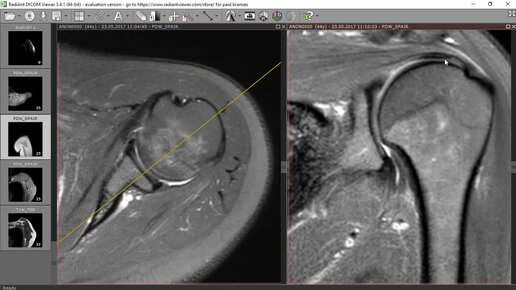

Базовый курс по МРТ- a. Лекция «МР-анатомия плечевого сустава и методика сбора данных». Лектор- Учеваткин А.А._3